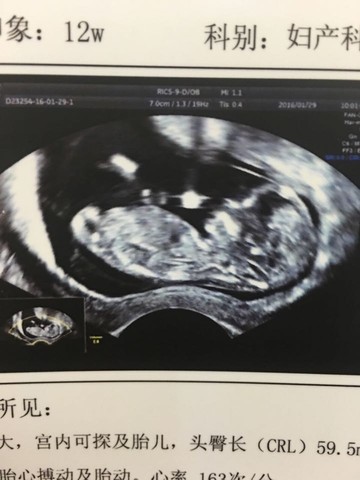

之前发过一个害怕胎停的帖子,好多宝妈各种安慰我,今天12周整,终于做了NT,宝宝第一张清晰的照片终于看到啦谢谢之前给我加油的宝妈们,希望我还有八月圈的所有猴妈妈都可以顺利平安生下小猴子 我之前自然流产过一次,为了保险起见我去医院生殖科做了大部分比较重要的检查,主要是免疫方面和凝血方面的,没有问题。我老公也查了精子。所以各位胎停流产的妈妈们,我觉得最基础的孕前检查不解决问题,要去生殖科,祝大家早日好孕